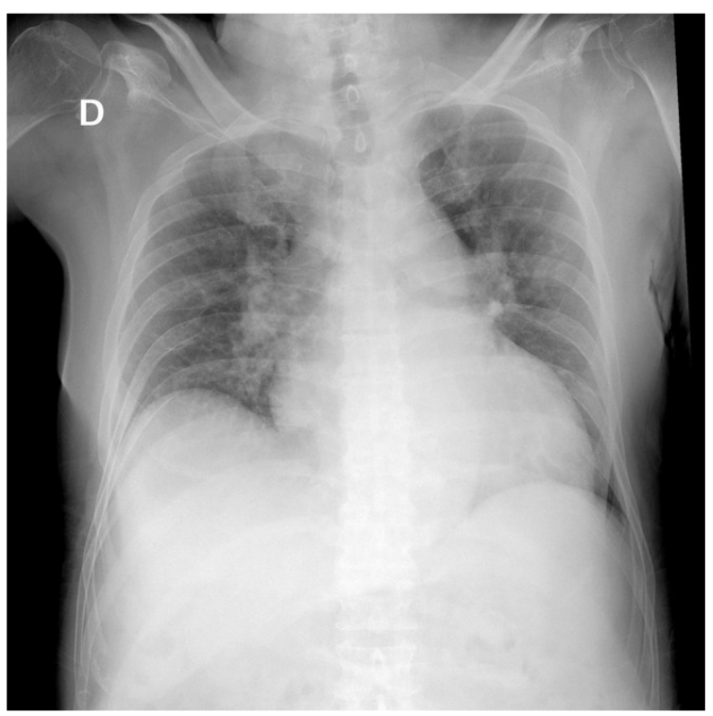

Ingresa a hospitalización y se toman los paraclínicos, los cuales reportan: péptido natriurético tipo B (NT PROBNP): muy elevado de 66.526, electrocardiograma (ECG) con ritmo sinusal, eje desviado a la izquierda y sin trastorno de la repolarización del segmento ST; radiografía de tórax con opacidades en vidrio deslustrado, sin consolidaciones, cardiomegalia y derrame pleural bilateral (figura 1); ecocardiograma transtorácico (ECO TT), donde se evidencia una cardiopatía isquémica con hipertrofia excéntrica del ventrículo izquierdo (VI) con alteraciones de la contractilidad y disfunción sistólica severa, una fracción de eyección del ventrículo izquierdo (FEVI) del 30 %, STRAIN global longitudinal de -7,3 %, disfunción diastólica moderada y una severa dilatación de la aurícula izquierda (AI); además de hipertensión pulmonar de PSAP de 49 mmHg (probabilidad intermedia), ventrículo derecho de tamaño y función normal (figura 2).